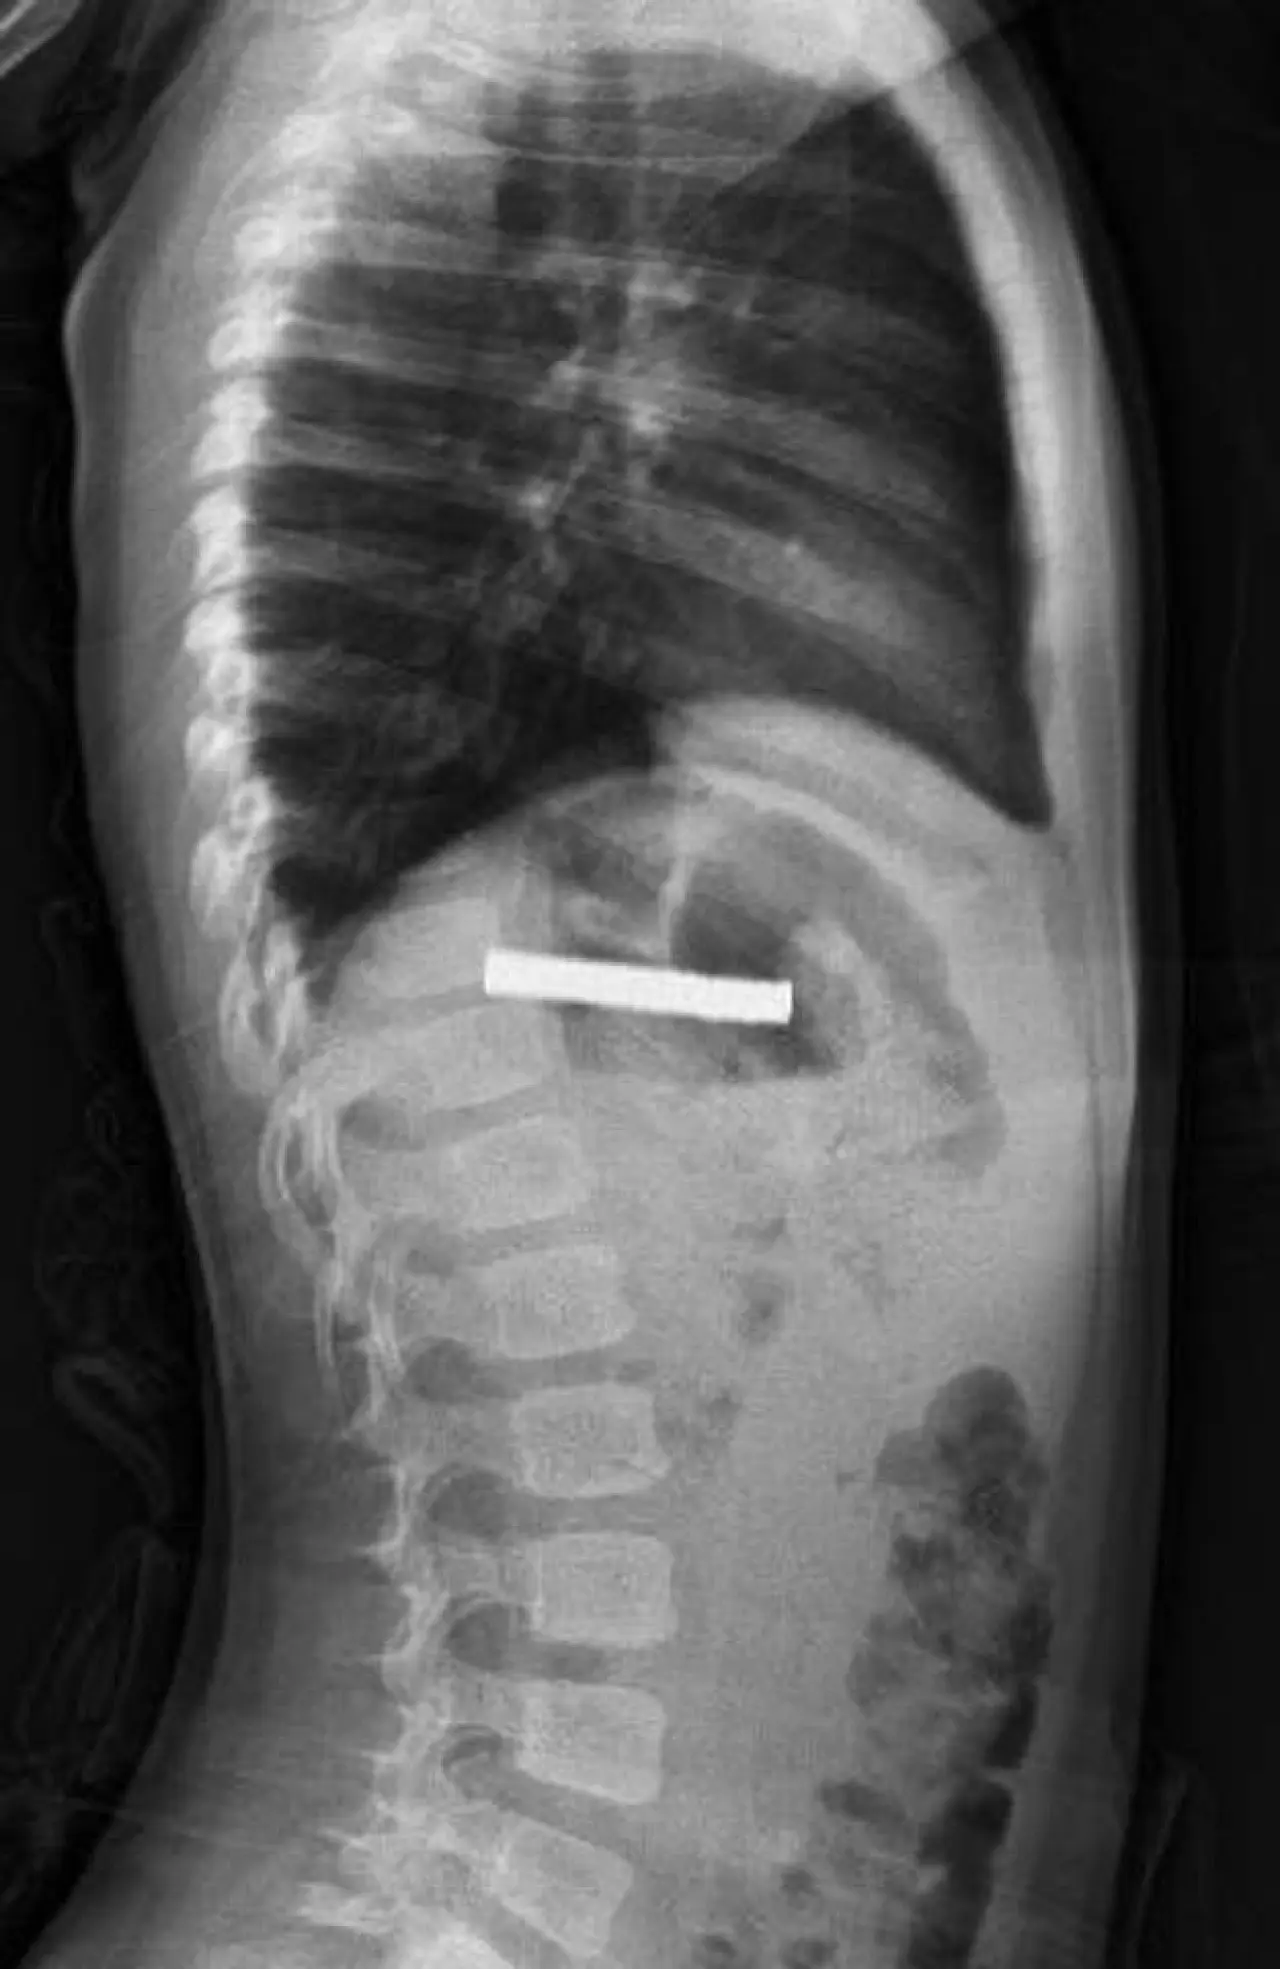

Edinilen bilgiye göre, Erzurum’da evde oyun oynarken bulduğu mıknatısları yutan çocuk, rahatsızlanınca Erzurum Şehir Hastanesi’ne kaldırıldı. Tetkiklerin ardından durumun ciddiyeti nedeniyle ambulans helikopterle Fırat Üniversitesi Hastanesi’ne getirildi. Çocuk Gastroenteroloji Hepatoloji ve Beslenme Bilim Dalı Başkanı Prof. Dr. Yaşar Doğan, mıknatısların yemek borusunda yapışarak tıkanıklığa yol açtığını tespit etti.

Operasyonla ilgili AA’ya bilgi veren Doğan,

“Mıknatıslar uzun süre yemek borusunda kaldığı için hasar bırakmıştı. Çok güçlü mıknatıslardı. İşlemi kolaylaştırmak için mıknatısları yemek borusundan mideye aldık ve özel bir fileyle çıkardık. Hastayı gece boyunca gözlem altında tuttuk. Genel durumu iyi olan çocuğu, ailenin isteği üzerine sabah taburcu ettik.”